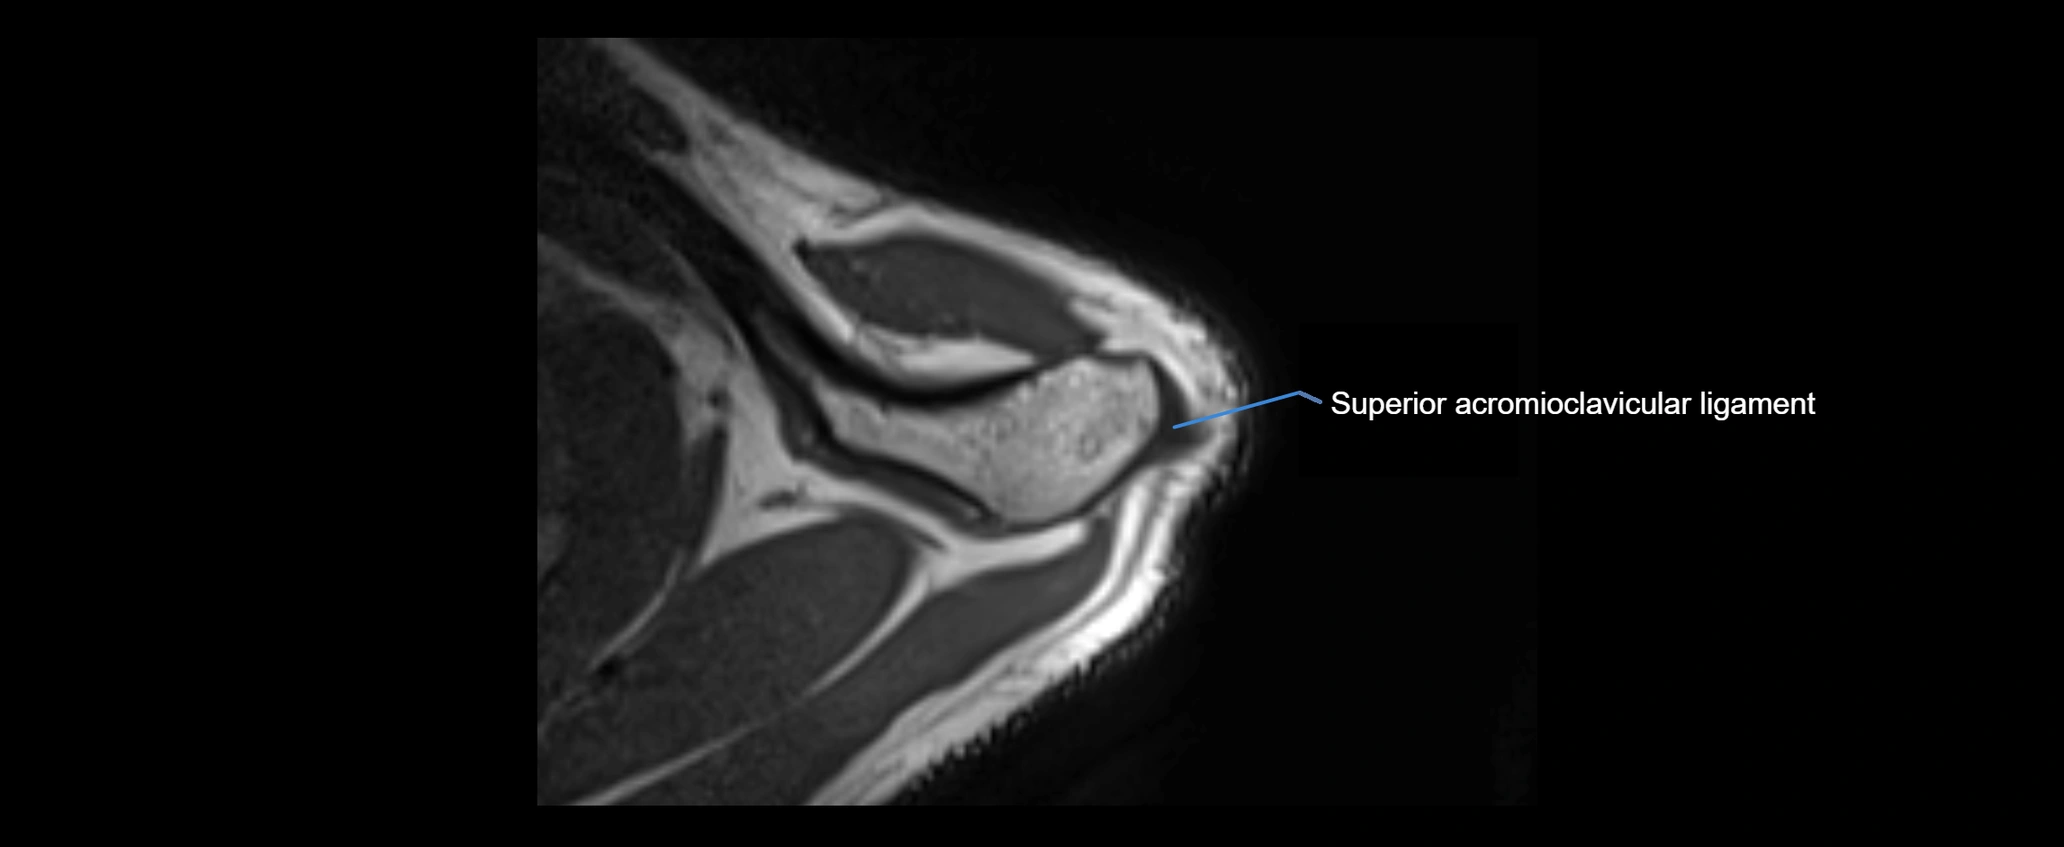

MRI images

image

MRI Appearance

• T1-weighted images:

• Normal ligament: Low signal (dark linear band) spanning acromion to clavicle.

• Surrounding fat planes: Bright, delineating the ligament clearly.

• Marrow of clavicle and acromion: Bright due to fatty content.

• Tears: Discontinuity or irregular thickening with intermediate-to-bright signal.

• Chronic injury: Thinning, fraying, or irregular low-signal fibers with adjacent scarring.

• T2-weighted images:

• Normal ligament: Low signal, homogeneous.

• Partial tear or sprain: Focal hyperintensity or thickening.

• Complete tear: Discontinuity with fluid-bright gap between clavicle and acromion.

• Associated edema: Bright signal in distal clavicle or acromion marrow.